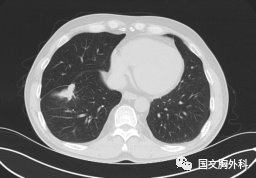

這個(gè)病人檢查胸部CT如圖3:根據(jù)影像學(xué)考慮是惡性腫瘤,行手術(shù)治療后病理回報(bào):“肺膿腫,合并炎癥纖維組織增生”,因此“肺占位”不代表就是惡性腫瘤,診斷金標(biāo)準(zhǔn)是病理診斷。如果檢查后發(fā)現(xiàn)“肺占位”先不要驚慌,及時(shí)就診請(qǐng)專(zhuān)科醫(yī)生會(huì)診指導(dǎo)治療才是關(guān)鍵。